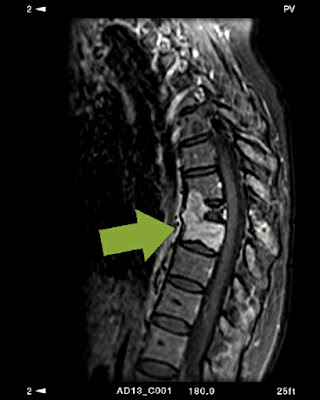

Πλασματοκύττωμα Θωρακικής μοίρας.